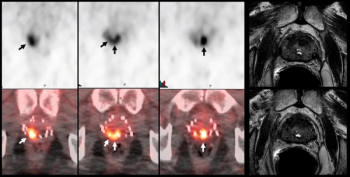

In an analysis of patients with intraprostatic/prostate bed findings of biochemical prostate cancer recurrence, the use of 18F-DCFPyL PET/CT led to an 82.3 percent cancer detection rate in comparison to 80 percent for multiparametric MRI, according to research presented at the recent Society for Nuclear Medicine and Molecular Imaging (SNMMI) conference.